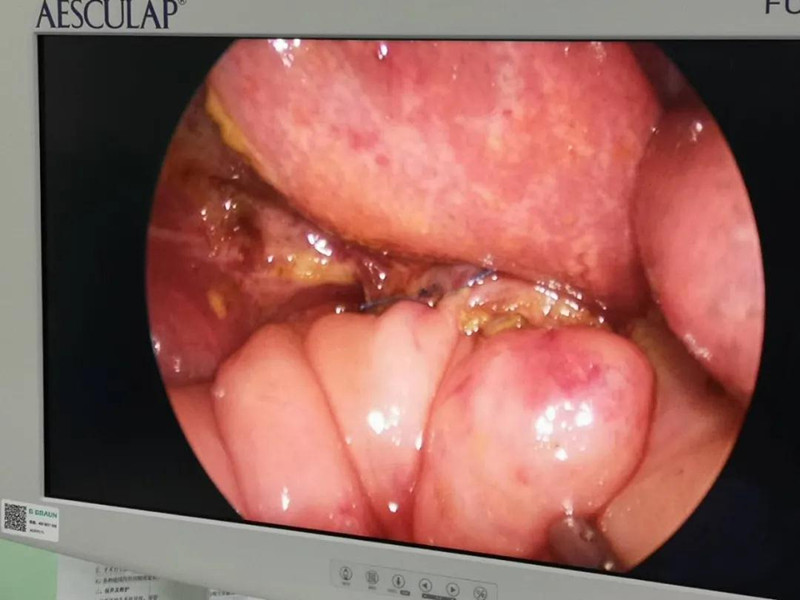

最近半个月,长春市26个月女宝馨馨(化名)脸色不好,全身发黄严重,还伴随发烧。9月23日,馨馨被家人带到蜜桃视频 诊治。经检查,馨馨全身发黄是因为患有黄疸,而黄疸的出现是因为胆总管发生病变,“胆总管呈现囊性扩张,下边出口被堵住,胆汁进不到肠腔里,导致孩子出现黄疸、肝功不好、白土便症状。而且胆总管胀大后,还有癌变的风险,”普外、新生儿外科主任崔钊说,馨馨需要尽快手术。为了减少损伤,崔钊主任团队制定的方案是单孔腹腔镜下胆总管囊肿根治手术。

术前准备完毕。 9月25日,馨馨进入手术室。由崔钊主任带队,按照术前设计的方案,经过8个小时的奋战,手术成功了。馨馨肝总管以下病变的胆总管及胆囊全部切除,肝总管断面与肠管吻合接上,让胆汁直接流到肠腔里,帮助消化。如术后不出现胆瘘、肠瘘,没有梗阻,馨馨以后就可以正常生活了。目前馨馨恢复得很好,黄疸渐渐缓解,肝功正常,白细胞也降下来了,排气、排便都没问题,引尿管里也没有异常东西。